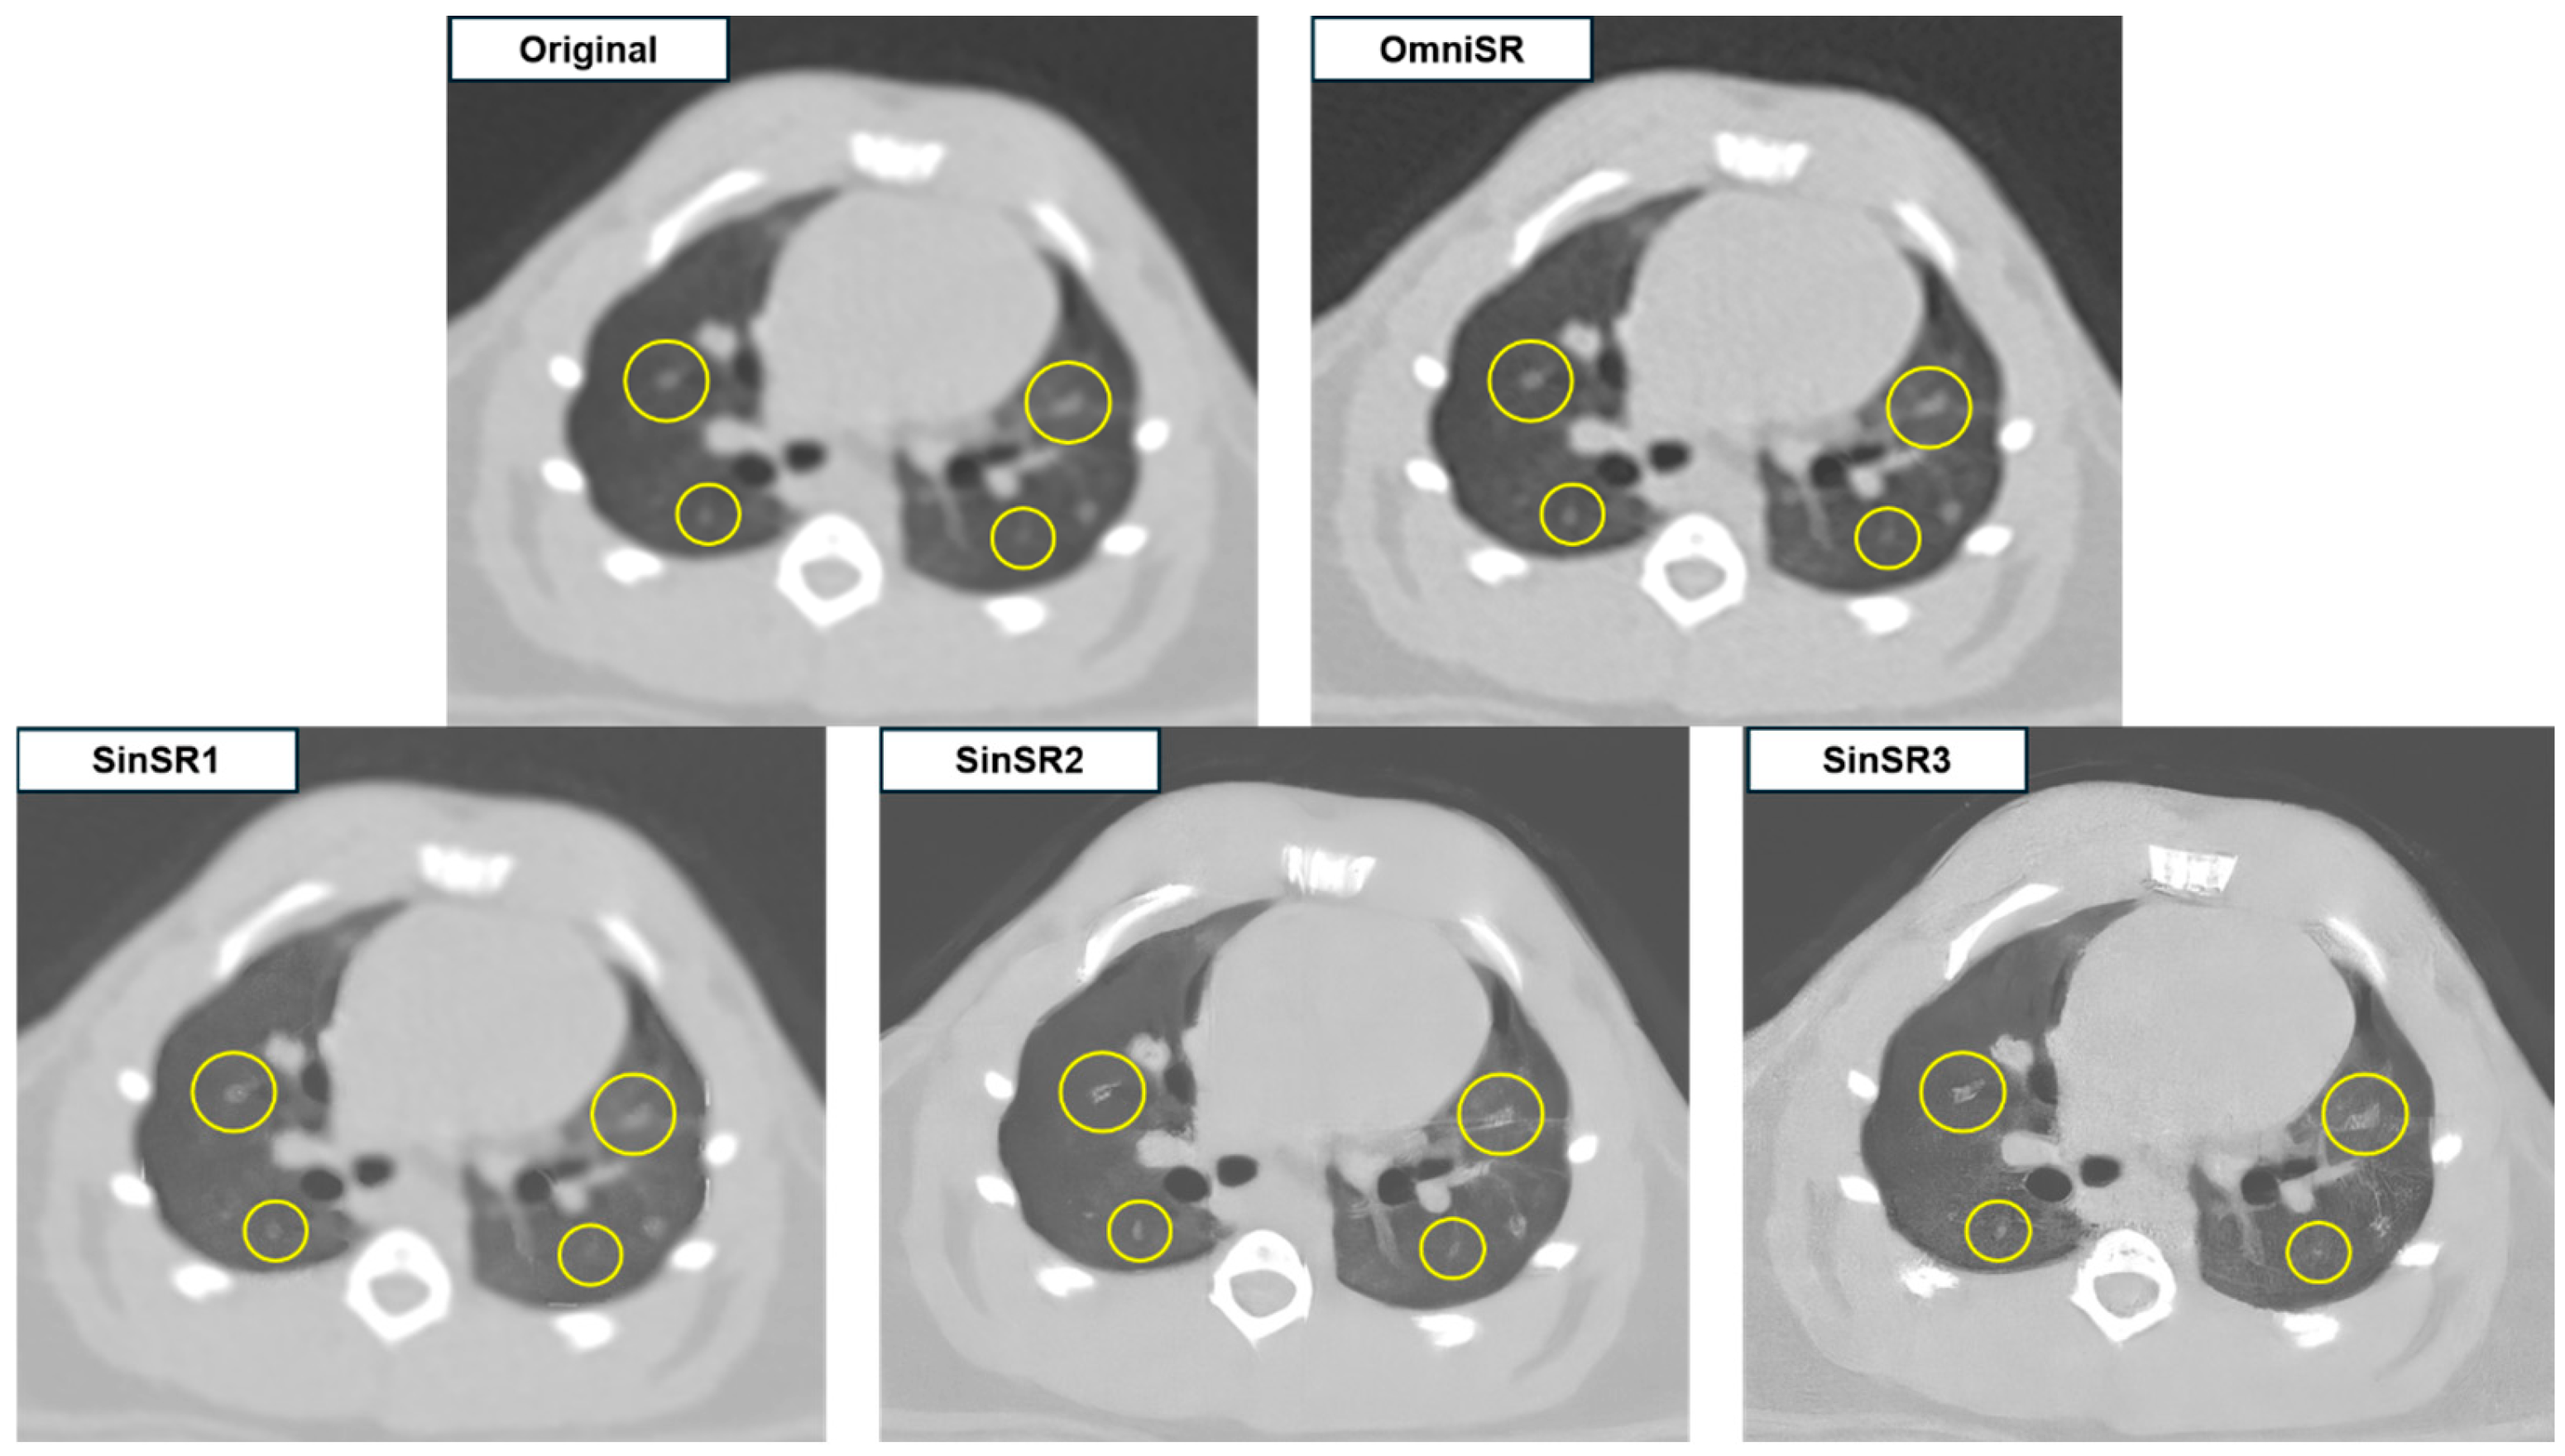

3.2. Subjective Image Analysis

| Anatomic structure similarity | R1 | 3.00 ± 0.00 | 1.00 ± 0.00 | 1.00 ± 0.00 | 2.06 ± 0.91 | N/A |

| R2 | 3.00 ± 0.00 | 1.00 ± 0.00 | 1.00 ± 0.00 | 2.20 ± 0.90 | N/A | |

| Mean | 3.00 ± 0.00 | 1.00 ± 0.00 * | 1.00 ± 0.00 *† | 2.13 ± 0.90 *§ | <0.001 | |

| Overall image quality | R1 | 4.78 ± 0.42 | 1.66 ± 0.74 | 1.77 ± 0.71 | 3.14 ± 0.79 | N/A |

| R2 | 4.71 ± 0.48 | 1.65 ± 0.73 | 1.76 ± 0.70 | 3.08 ± 0.77 | N/A | |

| Mean | 4.75 ± 0.45 | 1.66 ± 0.73 * | 1.77 ± 0.70 *† | 3.11 ± 0.78 *§ | <0.001 |